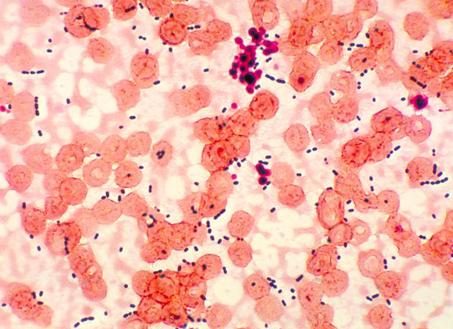

Доминирует в теле человека Enterococcus faecalis – фекальный энтерококк. Он – это 80-90% всей популяции. Ему помогает Enterococcusfaecium, составляет 5-10% микрофлоры. Именно их можно встретить в мазке у женщин. Ранее они плохо диагностировались, поскольку напоминают внешне стрептококки и обнаружить их в мазке было достаточно сложно. Но теперь, когда всё больше информации есть о бактерии, она стала более узнаваемой. Обнаружить её в мазке помогает современная техника и технологии. Именно благодаря соответствующему оборудованию так легко определить нормальное количество и патологию в мазке у женщин. Догадаться же, что необходимо сдать анализы внепланово можно по таким симптомам:

Ранее энтерококков не выделяли отдельно, а относили к группе стрептококков класса Д, но по современным классификациям их выделили отдельно. Эти микробы относятся к группе грамположительных микробов, их сегодня насчитывается около 15 видов, хотя не все еще хорошо изучены и классифицированы.

Энтерококки – это мелкие, круглой формы микробы, не образующие капсул и спор, они могут жить в условиях отсутствия кислорода в организме, или в кислородной среде. Поэтому, они широко распространены и достаточно устойчивы к факторам внешней среды. Расти микробы могут при плюсовых температурах, но самыми оптимальными для них являются 37-39 градусов, то есть температура внутри тела. Энтерококк может длительно сохраняться во внешней среде, устойчив к средствам дезинфекции и может жить на различных поверхностях в доме, он хорошо выдерживает кипячение и нагревание. Энтерококки являются достаточно частыми возбудителями различных заболеваний – так, зачастую они повинны в развитии инфекции мочевых и половых путей, инфекций внутри брюшной полости, поражений органов малого таза, а также могут вызывать осложнение раневых процессов, поражений сердца с формированием эндокардита. На долю энтерококка приходится до 10% от всех внутрибольничных инфекций, особенно в отношении мочевых путей, раневых процессов и общих септических процессов. Однако, параллельно  этим, энтерококки являются составной частью нормальной микрофлоры человеческого желудочно-кишечного тракта, могут играть важную роль в формировании защитных свойств в области слизистых оболочек тонкого и толстого кишечника и формирования кишечного иммунитета. Энтерококки в основном обитают в области тонкого кишечника, хотя достаточно значительное их количество обитает и в области толстой кишки. Обнаруживают энтерококки и в области мочеиспускательного канала у мужчин и женщин, детей, в области половых органов, а также на слизистых оболочках полости рта. Клинические материалы со всех возможных областей тела человека в подавляющем большинстве своем содержат фекальный энтерококк, и оставшиеся часть составляет энтерококк фэсциум. Все остальные энтерококки никак не относятся к вариантам нормальной микрофлоры кишечника и могут быть либо заносными и непатогенными, либо опасными в плане здоровья. Если определяться с количеством энтерококков в кишечнике, то в среднем от всего объема микрофлоры они составляют около 1%, то есть их в сто с лишним раз меньше, чем бифидофлоры и лактофлоры, у детей нормами энтерококка является его количество в одном грамме фекалий – 10 в 6-10 в 7 степени. Заселение кишечника этими микробами происходит у детей в первые часы жизни, при первых прикладываниях ребенка к груди, у искусственников процесс заселения микробной флорой кишечника идет труднее и дольше, так как они получают микробов с предметов, воздуха и рук персонала. Если рассматривать патогенные свойства энтерококков – то отдельные его штаммы могут вызывать инфекции моче-полового тракта у детей и взрослых, особенно если перед этим пациенты принимали большое количество антибиотиков, препаратов, подавляющих иммунитет или подвергались различным инвазивным методам обследования.